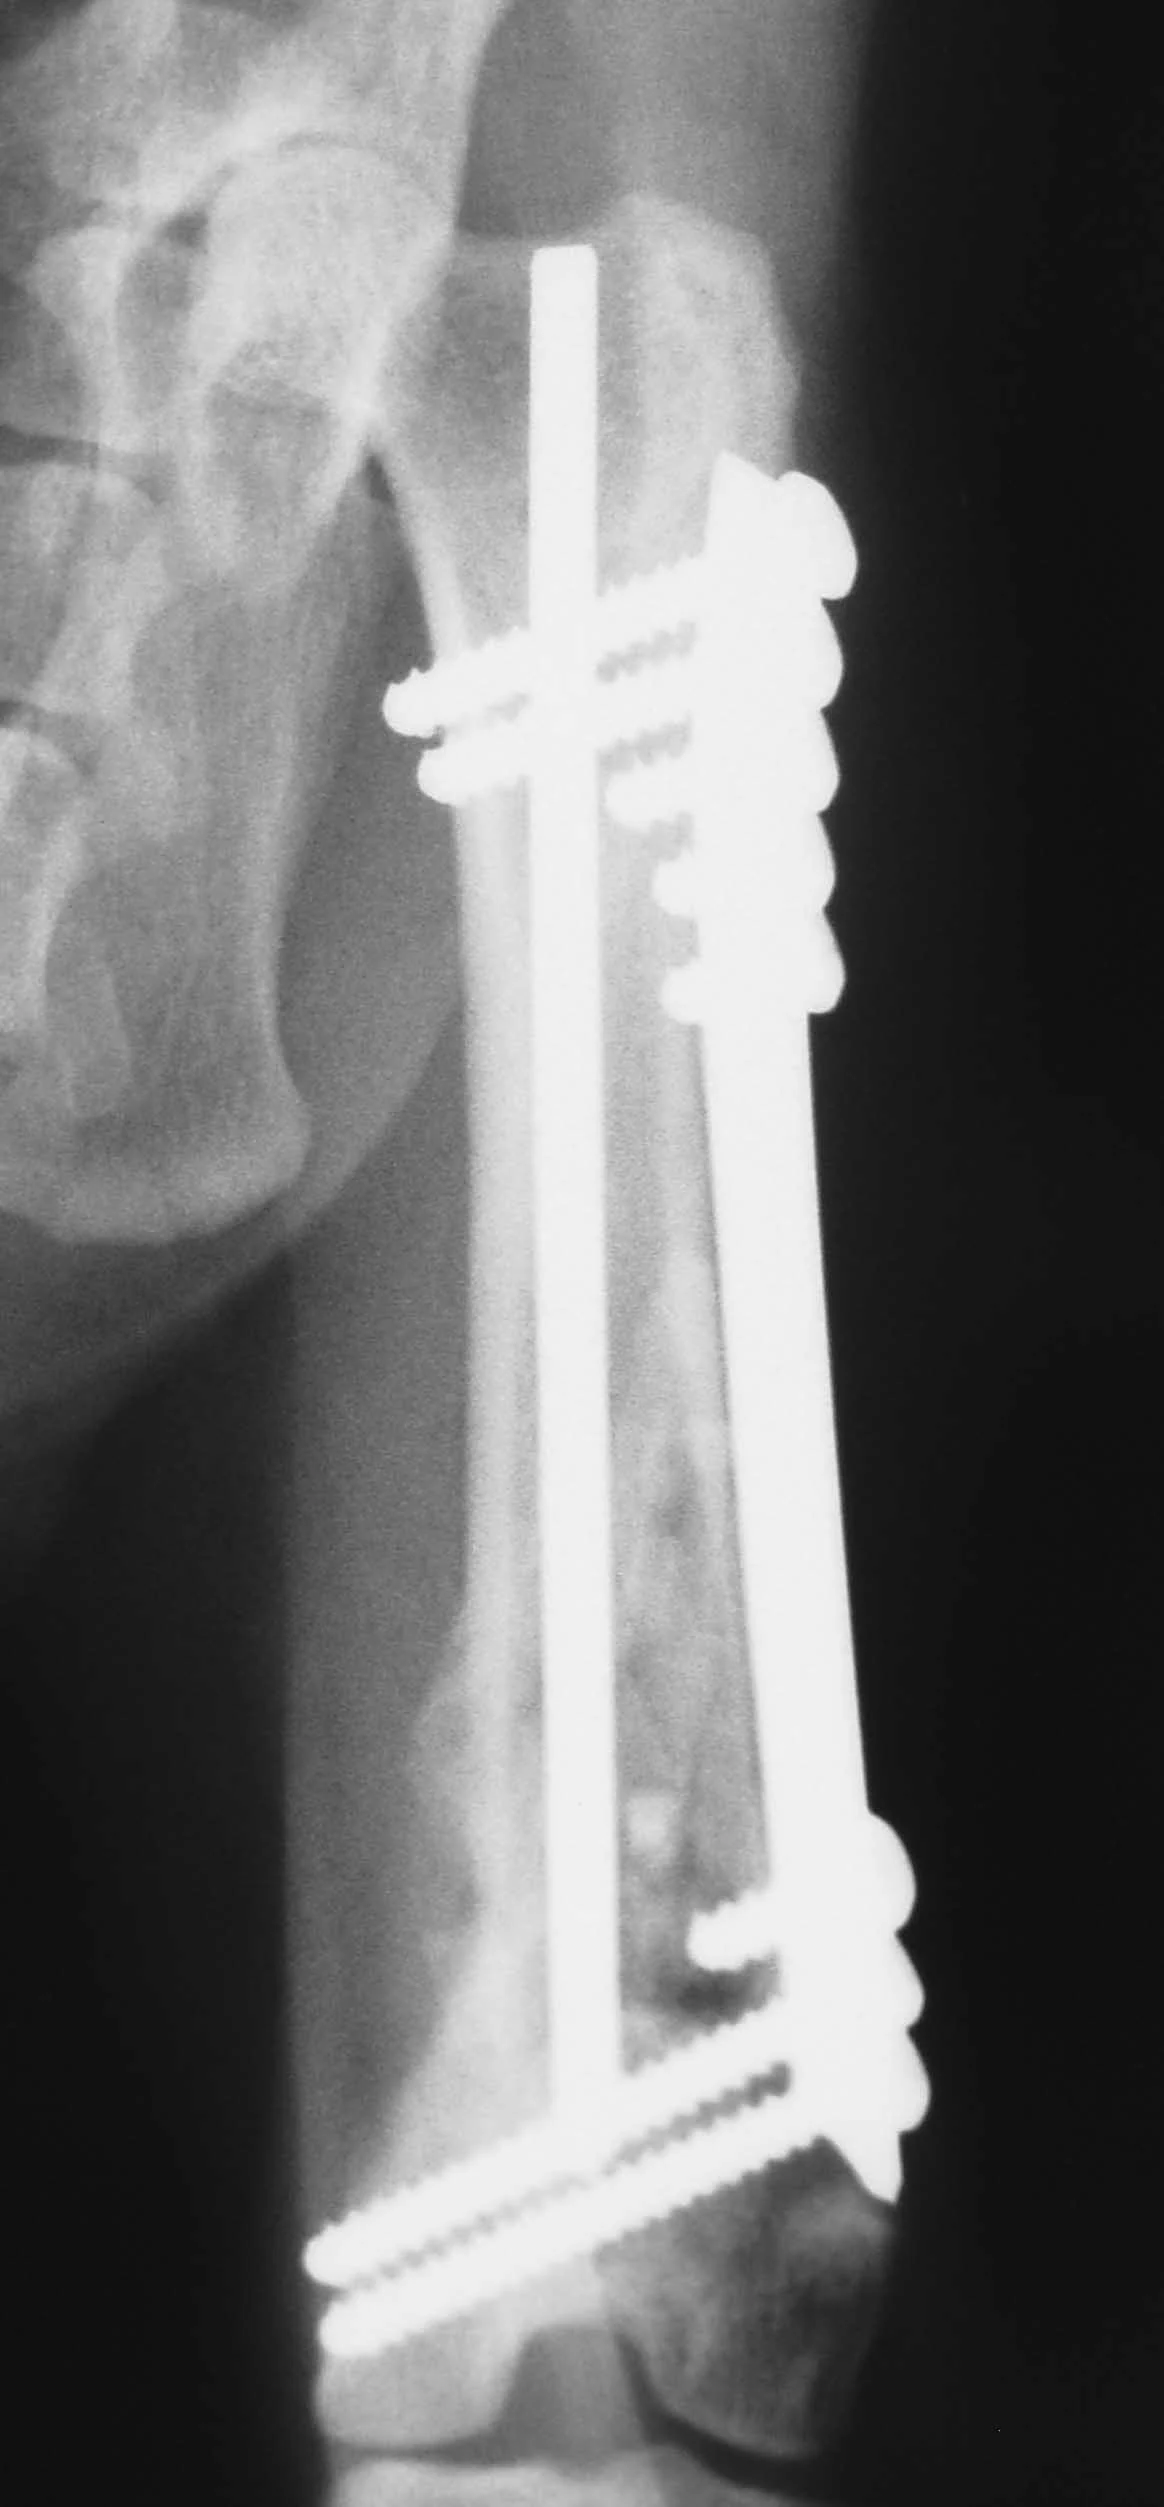

The combination of an IM pin and a bone plate has been found to be an ideal implant system for biologic management of comminuted fractures (Figure 1A) in dogs7 and cats. Adding an IM pin to the plate (Figures 1B, C) significantly increases stiffness and the estimated number of cycles to fatigue failure when compared with a plate-only system.

Adding an IM pin to a bone plate has been shown to reduce strain on the plate two-fold and subsequently increase the fatigue life of the plate-rod system 10-fold compared with the plate alone.2 In the canine femur, plate strain is reduced by approximately 19%, 44%, and 61% with the addition of an IM pin occupying 30%, 40%, and 50% of the marrow cavity, respectively.3

The IM pin is applied first. It can be used to assist distraction of the fracture as it engages the distal fragment. The pin provides axial alignment and provides partial stability for application of the plate.

The surgeon must be careful to attain rotational alignment before placing the screws of the bone plate. Only two to three screws are needed in the proximal and distal fragment. Monocortical screws are placed if the screw cannot be directed to avoid the IM pin. Open screw holes are protected by the IM pin and early bone callus, decreasing the chance of plate breakage.